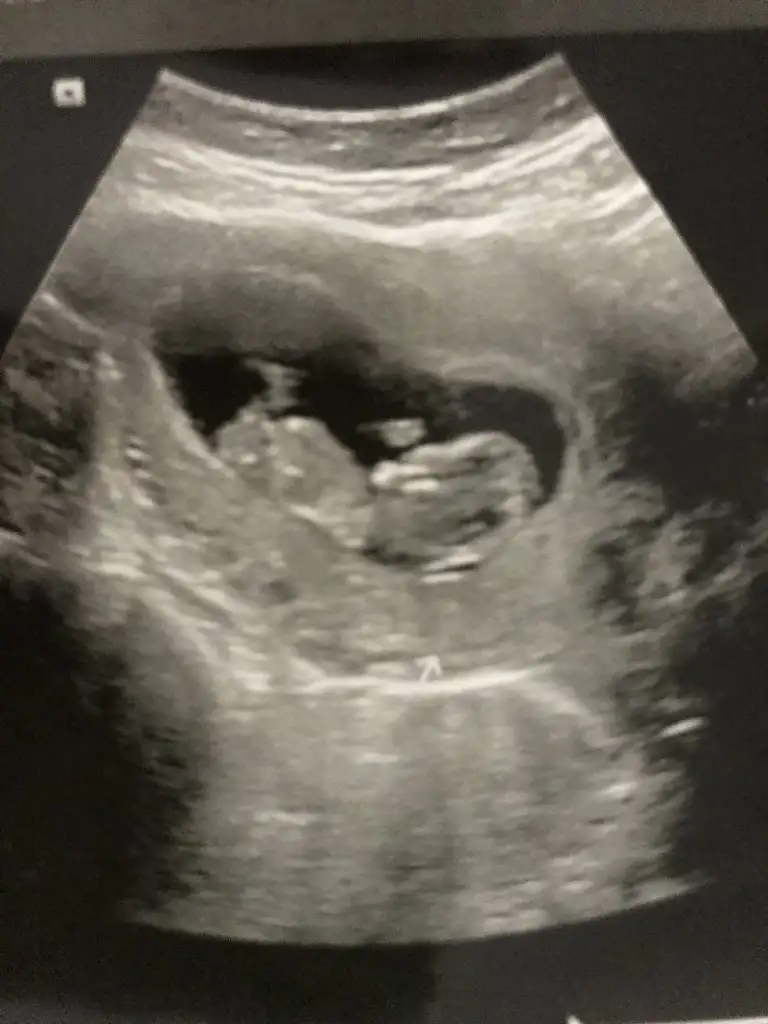

Bende kesin birşey demiyorum canım emin olamadım hayırlısı olsunValla canım ben hiç anlamıyorum nubtan falan sen maşallah çizmişsin bir deyan profilden göstertiginde biberon ucu gibi sivri dik bisey gösterdi biz bu dikligi görünce erkek diye yorumlarız dedi sonra bacak arasını da açıp gösterince evet burda da erkek görünüyor dedi ama yinede bir dahaki kontrolde daha netleşir dedi. Hatta ben kız hissediyorum babamız erkek hissediyor dedim baba haklı çıkacak sanırım dedi. Hayırlısı bakalım sağlıklı sıhhatli olsunda ❤

Erkek görünüyor

11 12 13 haftalar olmalıIkra meyra yorumlarmisiniz

Zaten 11 hafta11 12 13 haftalar olmalı